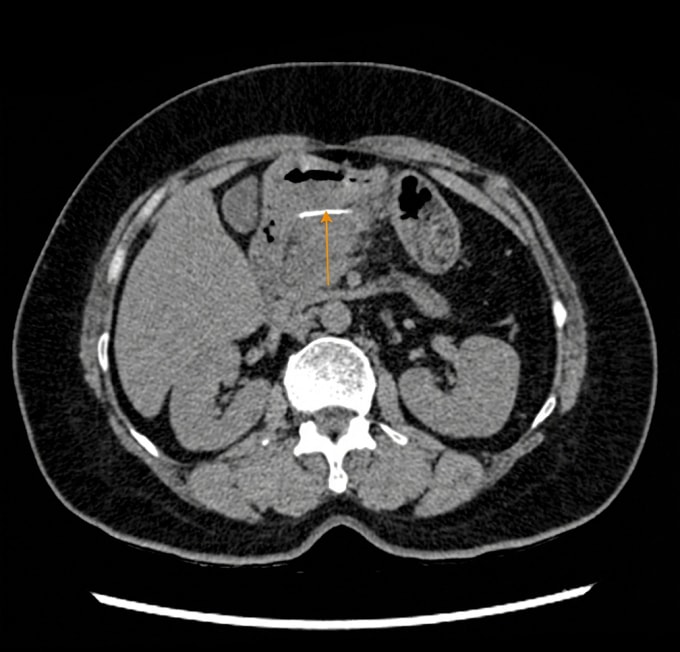

Kết quả chụp CT tại Bệnh viện Đa khoa Tâm Anh TP HCM cho thấy một dị vật dài khoảng 3 cm, mảnh, nằm ở hậu cung mạc nối, sát thành môn vị dạ dày. Bà Mỹ không biết mình nuốt phải dị vật.

Thạc sĩ, bác sĩ Võ Nhật Trường, Trung tâm Nội soi và Phẫu thuật Nội soi Tiêu hóa, cho biết dị vật đã đâm xuyên toàn bộ thành dạ dày, tạo thành khối áp xe ở hậu cung mạc nối. "Dị vật không còn nằm trong lòng dạ dày nên không thể lấy qua nội soi như thông thường", bác sĩ Trường nói.